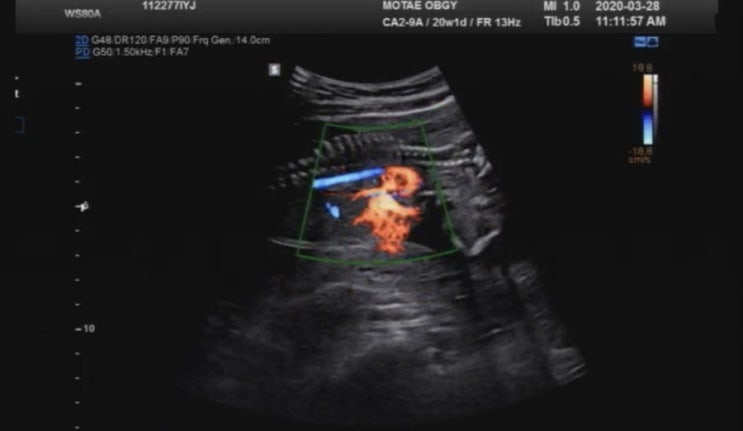

예비 달이맘_임신부터 출산 story_20주차_정기검진 정밀초음파 보고 왔답니다.(feat.염색체 질환 용어 및 초음파 용어 정리)

2020.03.28 Sat. 20주 1일차가 되는 날~정기검진으로 산부인과에 가는 날입니다. 정밀초음파를 보기로 한...